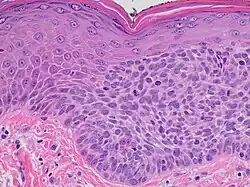

Histopathology

On histologic examination, actinic keratoses usually show a collection of atypical keratinocytes with hyperpigmented or pleomorphic nuclei, extending to the basal layer of the epidermis. A "flag sign" is often described, referring to alternating areas of orthokeratosis and parakeratosis. Epidermal thickening and surrounding areas of sun-damaged skin are often seen.[39] The normal ordered maturation of the keratinocytes is disordered to varying degrees: there may be widening of the intracellular spaces, cytologic atypia such as abnormally large nuclei, and a mild chronic inflammatory infiltrate.[8]

Specific findings depend on the clinical variant and particular lesion characteristics. The seven major histopathologic variants are all characterized by atypical keratinocytic proliferation beginning in the basal layer and confined to the epidermis; they include:[39]

- Hypertrophic: Notable for marked hyperkeratosis, often with evident parakeratosis.[39] Keratinocytes in the stratum malphigii may show a loss of polarity, pleomorphism, and anaplasia.[25] Some irregular downward proliferation into the uppermost dermis may be observed, but does not represent frank invasion.[25]

- Atrophic: With slight hyperkeratosis and overall atrophic changes to the epidermis; the basal layer shows cells with large, hyperchromatic nuclei in close proximity to each other. These cells have been observed to proliferate into the dermis as buds and duct-like structures.[25]

- Lichenoid: Demonstrate a band-like lymphocytic infiltrate in the papillary dermis, directly beneath the dermal-epidermal junction.[39]

- Achantholytic: Intercellular clefts or lacunae in the lowermost epidermal layer that result from anaplastic changes; these produce dyskeratotic cells with disrupted intercellular bridges.

- Bowenoid: This term is controversial and usually refers to full-thickness atypia, microscopically indistinguishable from Bowen's Disease.[25] However most dermatologists and pathologists will use it in reference to tissue samples that are notable for small foci of atypia that involve the full thickness of the epidermis, in the background of a lesion that is otherwise consistent with an actinic keratosis.[39]

- Epidermolytic: With granular degeneration.[25]

- Pigmented: Show pigmentation in the basal layer of the epidermis, similar to a solar lentigo.[39]